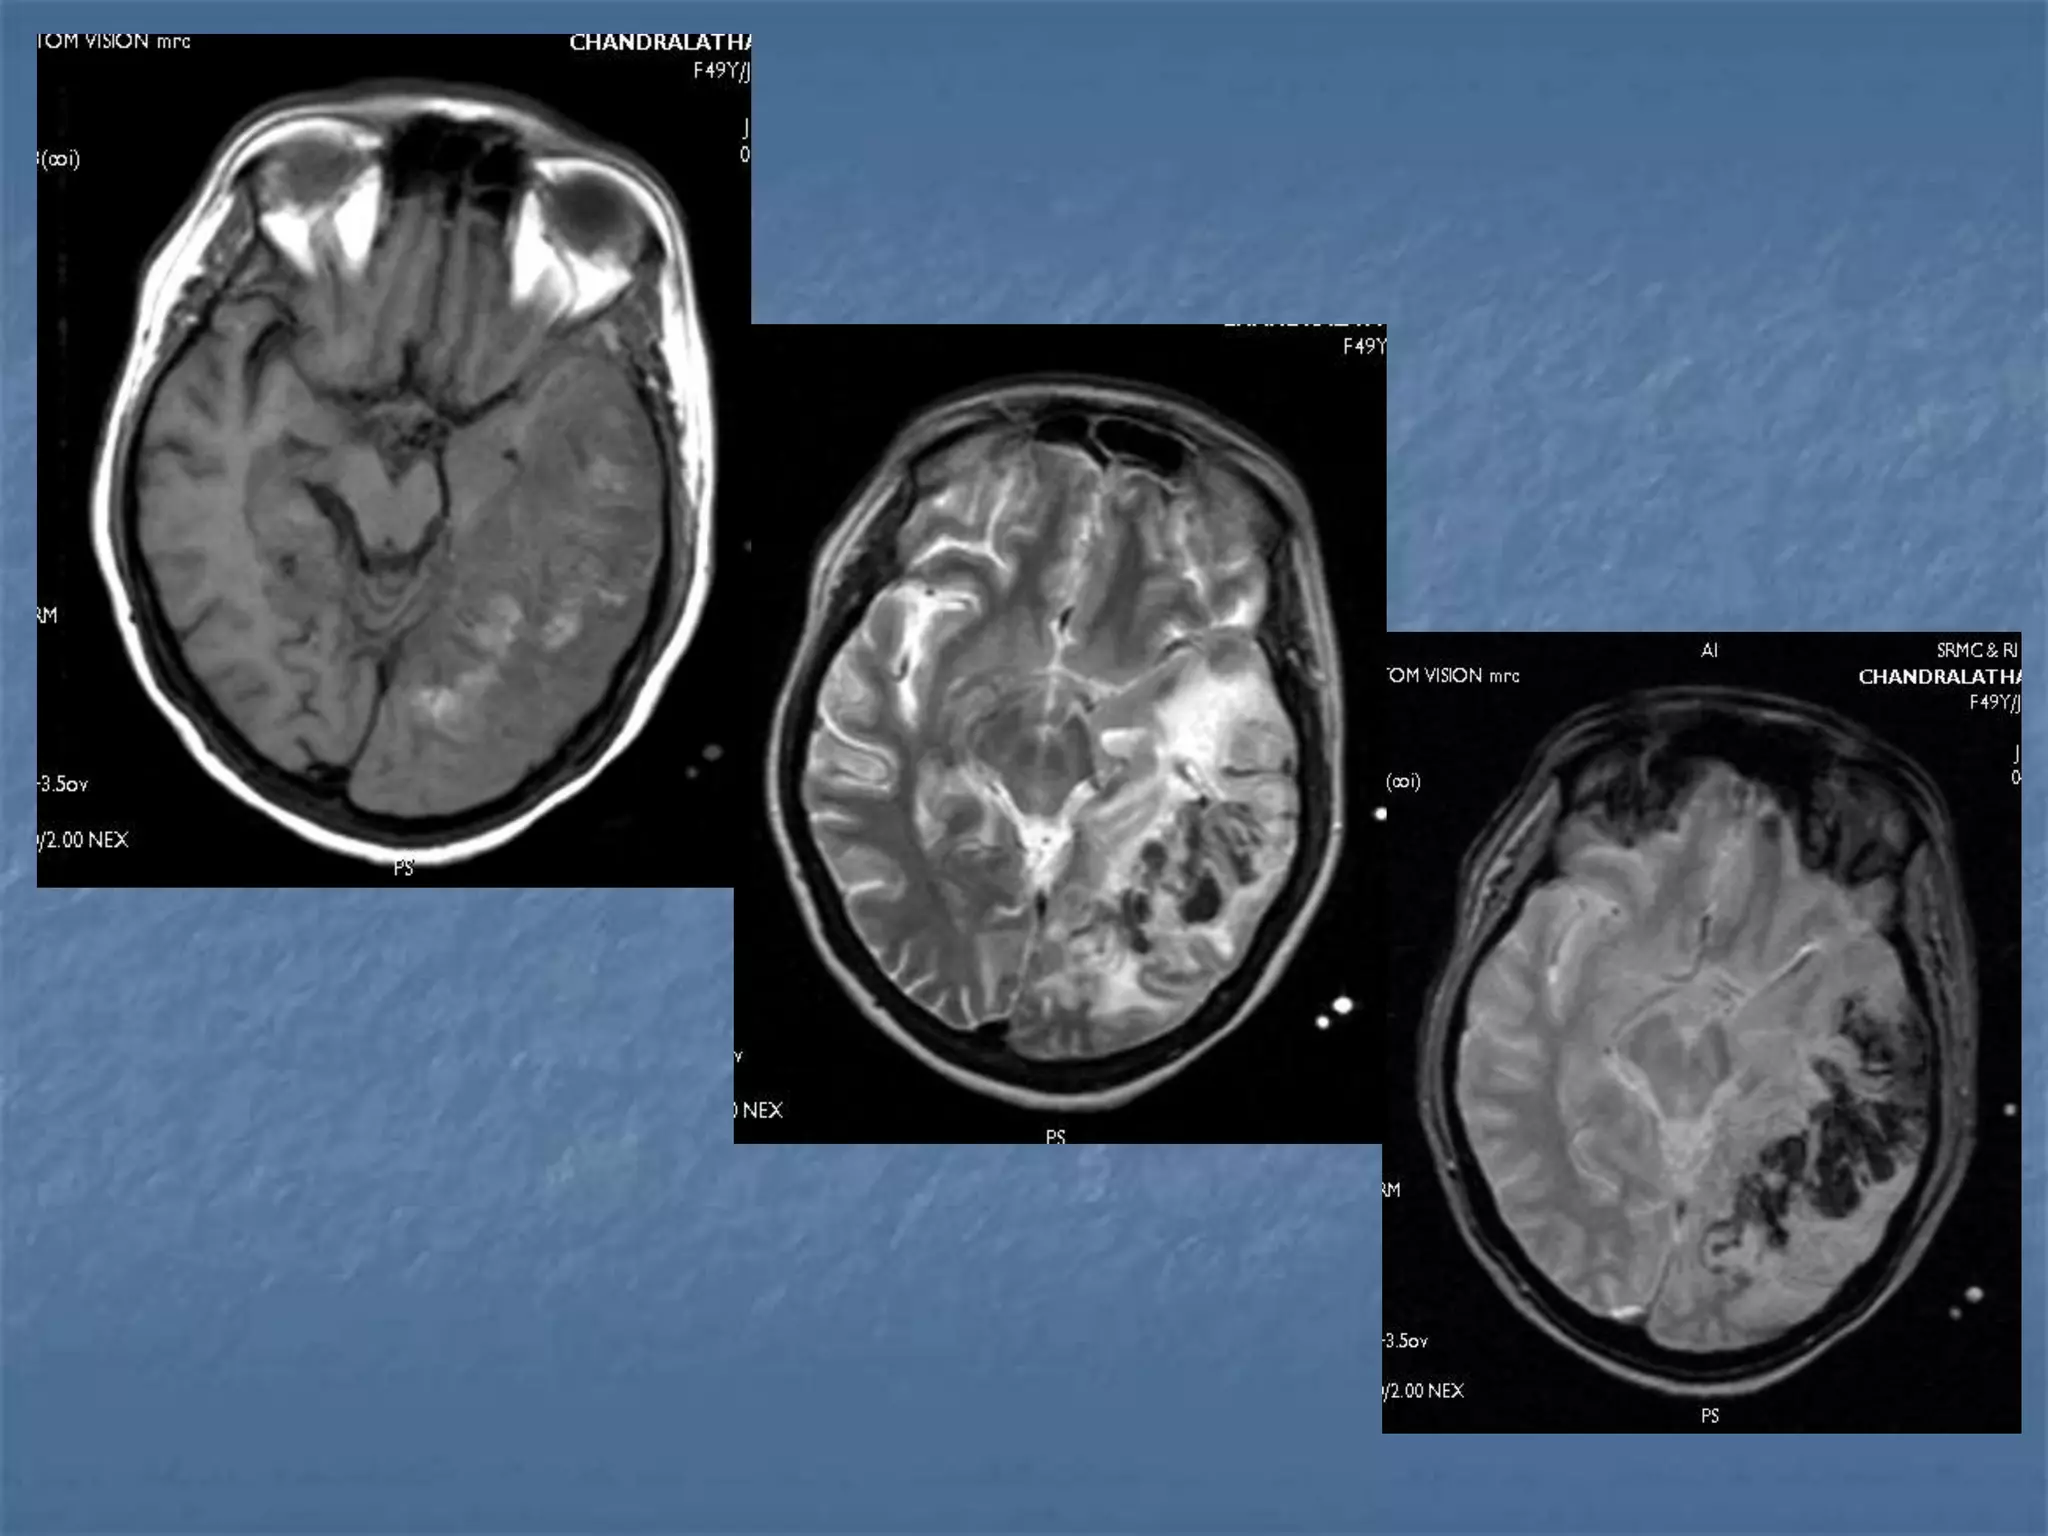

25 yr oldlady c/o fever and altered sensorium x 1 wk. Had 1 episode of GTC seizures. Admitted elsewhere , LP done showed proteins-55 mg % and sugar –105 mg % .. ABG- pH – 7.55 HCO3 – 28.3 , PCO2-32.9, PO2 –322.9,SPO2-99.8 CT – Normal Discharged at request. H/o fever,headache and vomitting on and off x 5 mths -

• 155.

 O/E –GCS – E1V1M5 BP – 140/100 , PR – 116 Pupils – 4mm dilated , sluggish light reaction Neck Rigidity + Kernig’s & Brudeski’s - ve  Hb-13.5  TC- 12,200  Platelets-4.2  MP/MF – negative  BUN, creatinine – normal  Urine R/E – proteins +++, pus cells 5-8  Coagulation Profile - WNL  134/3.4/26/102

Encephalitis CT scan is often normal , especially early in

the disease.

 Ill defined hypodense lesions may be seen

e.g. temporal lobe changes are predominant

in Herpes Encephalitis.

 MRI is far more sensitive in the evaluation of

patients with encephalitis

Encephalitis

 Diffuse nonfocal brain parenchymal

inflammatory process

 Most common agents - viruses

 Immunocompetent individuals - Herpes viruses

 Immunocompromised individuals

 Human immunodeficency virus (HIV)

 Cytomegalovirus (CMV)

 Papovavirus